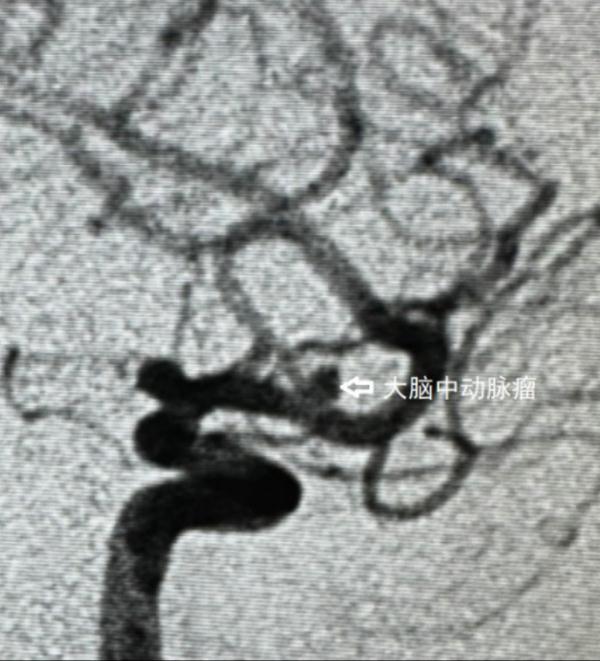

CT检查结果显示,姚江头颅右侧鞍旁明显结节状突起,蛛网膜下腔少许高密度影。进一步行头颅CTA检查,提示其右侧颈内动脉C7段后交通动脉起始处动脉瘤,左侧大脑中M1段动脉瘤。

经过5天的治疗护理,姚江再次接受了左侧大脑中动脉M1段动脉瘤支架辅助弹簧圈栓塞术。

经过精细的手术,左侧动脉瘤的危机也宣告解除。术后,患者无神经功能障碍,目前已经康复出院。